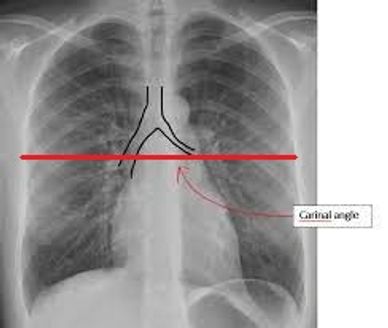

PLAN YOUR BOLUS TRACKER/SMART PREP/ROI JUST BELOW THE CARINA